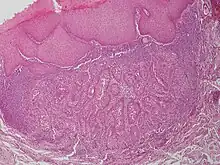

Warty dyskeratoma, also known as an Isolated dyskeratosis follicularis,[1]: 777 is a benign[2] epidermal proliferation with distinctive histologic findings that may mimic invasive squamous cell carcinoma[3] and commonly manifests as an umbilicated (Having a central mark or depression resembling a navel) lesion with a keratotic plug,[4] WD have some histopathologic similarities to viral warts but it's not caused by HPV and the majority of these lesions display overall histopathologic features consistent with a follicular adnexal neoplasm.[5] Usually limited to the head, neck,[6] scalp[7] or face and vulva.[6] Lesions are generally solitary and sporadic and may be associated with a follicular unit. Oral involvement,[4] particularly the hard palate, and genital involvement have been reported. it can also be thought of as one of the manifestations of focal acantholytic dyskeratosis, an epidermal reaction pattern that can be seen in several disorders, including Darier's disease and Grover's disease.[8]: 639 But the main Difference between Darier disease and Warty dyskeratoma, is that Darier disease inherited dermatosis (autosomal dominant) consisting of multiple keratotic papules on the face, trunk, and extremities, while WD occurs as an isolated, noninherited, single keratotic nodule mainly confined to the head and neck as mentioned earlier.[6]